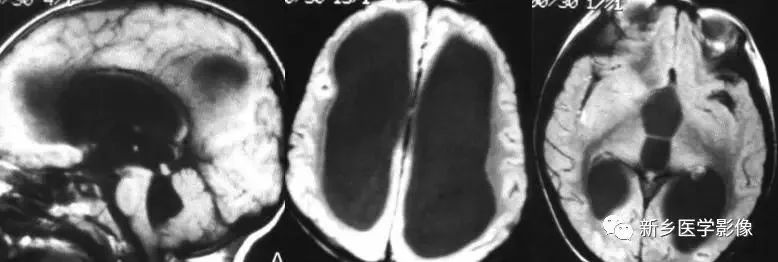

(1)前脑无裂畸形: (holoprosencephaly)是指一系列位于中线程度不同的畸形,累及大脑、面部、脑于和小脑.前脑未能够分开,呈不全性或完全性,端脑和间脑无法区分。根据脑及面部畸形程度将其分为无叶型、半叶型和单叶型。

无叶型前脑无裂畸形最严重.端脑半球间没有裂隙,呈马蹄形或新月形扩大的单脑室跨越中线,与背侧囊交通。丘脑互相融合,面部畸形从两眼距离过近到独眼畸形.往往死于胎儿或新生儿期。

半叶型前脑无裂畸形在前脑可见部分裂隙. 形成不同发育程度的大脑纵裂及大脑镰。两侧大脑半球在前部未完全分开,但枕叶和 双侧侧脑室体部分离,丘脑分开不完全。三脑室和海马发育不全,胼胝体仅可见到压部,而其他部分缺如.额叶和基底节前部分辨不清。临床表现有两眼距离过近.及唇裂、腭裂等面部畸形,侧脑室呈单一性.且明显扩大。

单叶型前脑无裂畸形与正常发育脑仅有些很小的区别.如透明隔缺如或双侧额叶不完全分开。